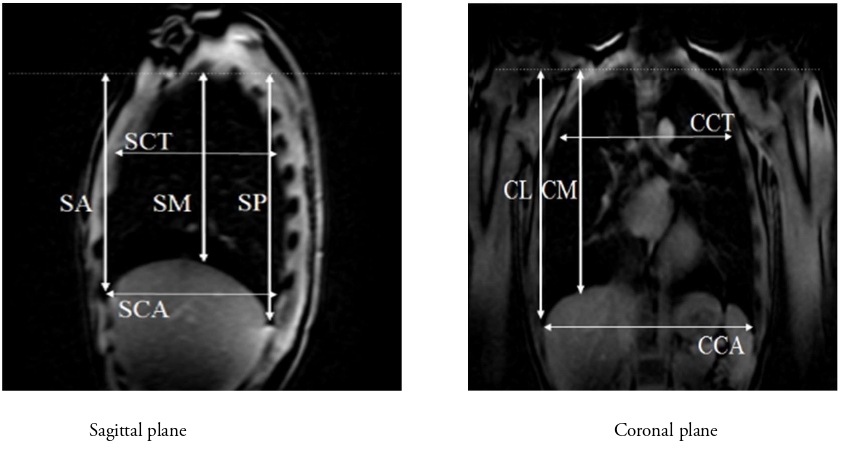

We used a 3.0T-MR Vintage Titan (Canon Medical Systems Corporation, Japan). The equipment was operated by physicians qualified as clinical radiologists and who were experienced in operating the MRI machine. Three-dimensional T1-weighted imaging and OsiriX (Newton Graphics) were used for analyzing MR data. The following lengths (Table 2) in the coronal plane (carina level) and sagittal plane (right midclavicular line level) were measured, and their ratio to height was calculated (Figure 3A and 3B).

Figure 3: Lung measurements by MRI. MRI: Magnetic Resonance Imaging; SA: Sagittal Anterior length; SM: Sagittal Mid-length; SP: Sagittal Posterior length; CCT: Coronal Carina Thoracic length; CCA: Coronal Carina Abdominal length; CM: Coronal Midclavicular length; CL: Coronal Lateral length.

Coronal plane (carina level) |

Coronal lateral (CL): Length from the lung apex to the lateral border of the thorax Coronal mid (CM): Length from the lung apex to the midclavicular line Coronal carina thoracic (CCT): Transverse length at the carina level Coronal carina abdomen (CCA): Maximum transverse length of the lower thorax |

Sagittal plane (right midclavicular line level) |

Sagittal anterior (SA): Length from the lung apex to the anterior lower edge. Sagittal mid (SM): Length from the lung apex to the lower edge of the midaxillary line. Sagittal posterior (SP): Length from the lung apex to the posterior lower edge Sagittal carina thoracic (SCT): Length from the lung anterior edge to the posterior edge of the upper thorax Sagittal carina abdominal (SCA): Length from the lung anterior edge to the posterior edge of the lower thorax |